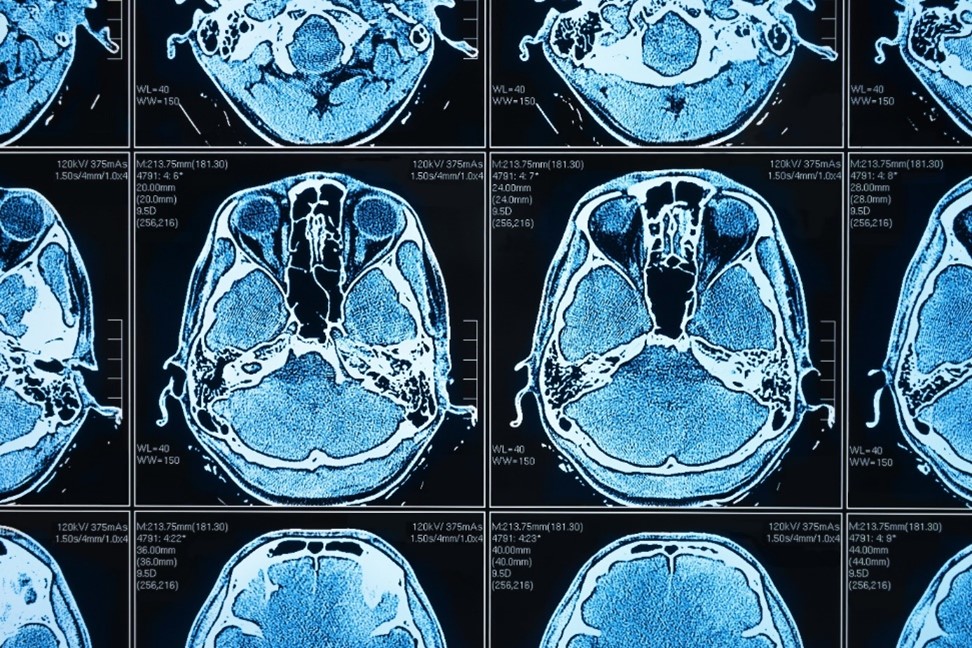

Künstliche Intelligenz (KI) und darauf gestützte Anwendungen werden in der medizinischen Praxis immer wichtiger. Und sie bieten unschlagbare Vorteile, beispielsweise in der Bildanalyse: Big-Data-Auswertungen und Massenverarbeitung von computergenerierten Dateien, Abgleich zwischen verschiedenen Datenbanken, Erkennung von Mustern und – fast noch wichtiger – von Abweichungen, Betrachtung von Entwicklungen im zeitlichen Verlauf, … die Liste der Anwendungsmöglichkeiten ist lang. Denn bei all diesen Aufgaben kann KI um ein Vielfaches effektiver und zuverlässiger „agieren“ als der Mensch.

Federated Learning in medizinischer Bildgebung (Quelle: Shutterstock)

Künstliche Intelligenz stellt eine ideale Ergänzung bei all jenen Aufgaben dar, die hohe Präzision und Effizienz erfordern. Gerade im Gesundheitswesen und insbesondere bei der Auswertung von bildgebenden Verfahren finden sich hier praktische Anwendungsszenarien en masse. Zudem ist künstliche Intelligenz bekanntlich trainierbar: Machine-Learning-Modelle erlauben es, große Datenvolumina in KI-Anwendungen einzuspeisen und diese entsprechend anzulernen, um zum gewünschten Abstraktionsniveau und damit zu belastbaren Ergebnissen zu kommen. Mit jedem neuen Datensatz wird die KI praktisch intelligenter und damit genauer.

Damit KI erfolgreich eingesetzt werden kann, braucht es umfangreiche und heterogene Trainingsdaten. Ein zuverlässiges Krebserkennungsmodell sollte beispielsweise auf der Grundlage von Tausenden von medizinischen Bildern trainiert werden, die gesundes Gewebe und Tumore im Vergleich aufzeigen können. Zugleich sollte das Modell auch die reale Bandbreite von Geschlecht, Alter und anderen demografischen Merkmalen der Patient*innen repräsentieren. Auch müssen visuelle Merkmale, die sich aus den verschiedenen Bildgebungstechniken ergeben, dargestellt werden.